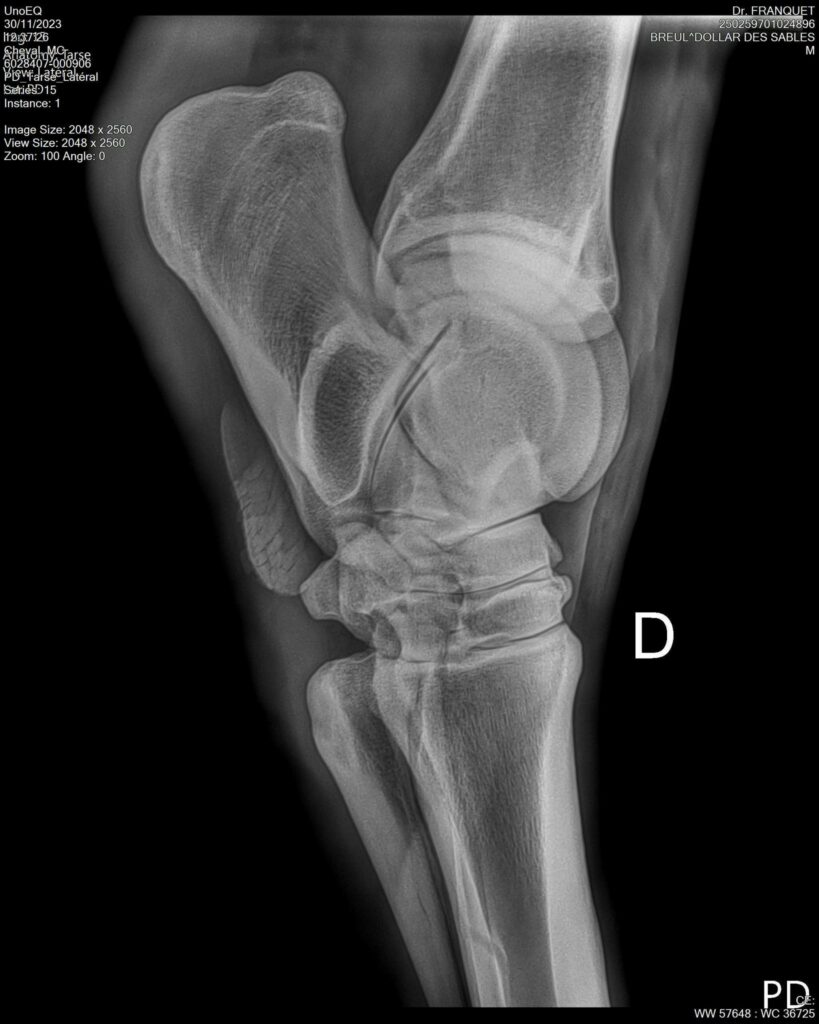

DOLLAR DES SABLES, Selle Français, hongre, 12 ans par DOLLAR DE MURIER x ABKE (ACORADO). Classé 135 avec professionnel à fait 125 avec amateur, récemment classé sur amateur 1GP 120. Très beau modèle ! Gentil cheval, respectueux avec des moyens et du sang. Transport OK, maréchalerie OK, santé RAS, Bilan clichés radios OK.

RADIOS